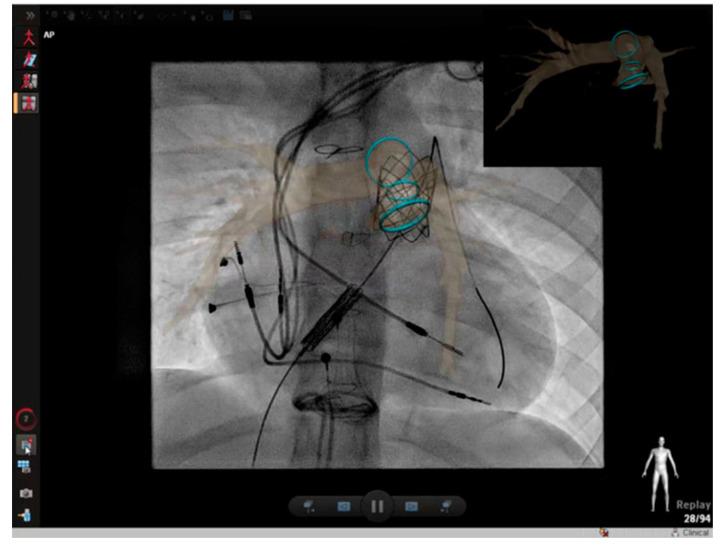

Management of congenital heart disease (CHD) has recently increased utilization of cross-sectional imaging to plan percutaneous interventions. Cardiac computed tomography (CT) and cardiac magnetic resonance (CMR) imaging have become indispensable tools for pre-procedural planning prior to intervention in the pediatric cardiac catheterization lab. In this article, we review several common indications for referral and the impact of cross-sectional imaging on procedural planning, success, and patient surveillance.

先天性心脏病(CHD)的管理最近增加了对横断面成像的利用,以规划经皮介入治疗。心脏计算机断层扫描(CT)和心脏磁共振(CMR)成像已成为小儿心导管实验室介入治疗前程序规划中不可或缺的工具。在本文中,我们回顾了转诊的几个常见指征以及横断面成像对程序规划、成功率和患者监测的影响。

Multimodality 3D image fusion with live fluoroscopy reduces radiation dose during catheterization of congenital heart defects.

Front Cardiovasc Med. 2024 Jan 11;10:1292039. doi: 10.3389/fcvm.2023.1292039. eCollection 2023.

3D advanced imaging overlay with rapid registration in CHD to reduce radiation and assist cardiac catheterisation interventions.

Cardiol Young. 2020 May;30(5):656-662. doi: 10.1017/S1047951120000712. Epub 2020 Apr 15.